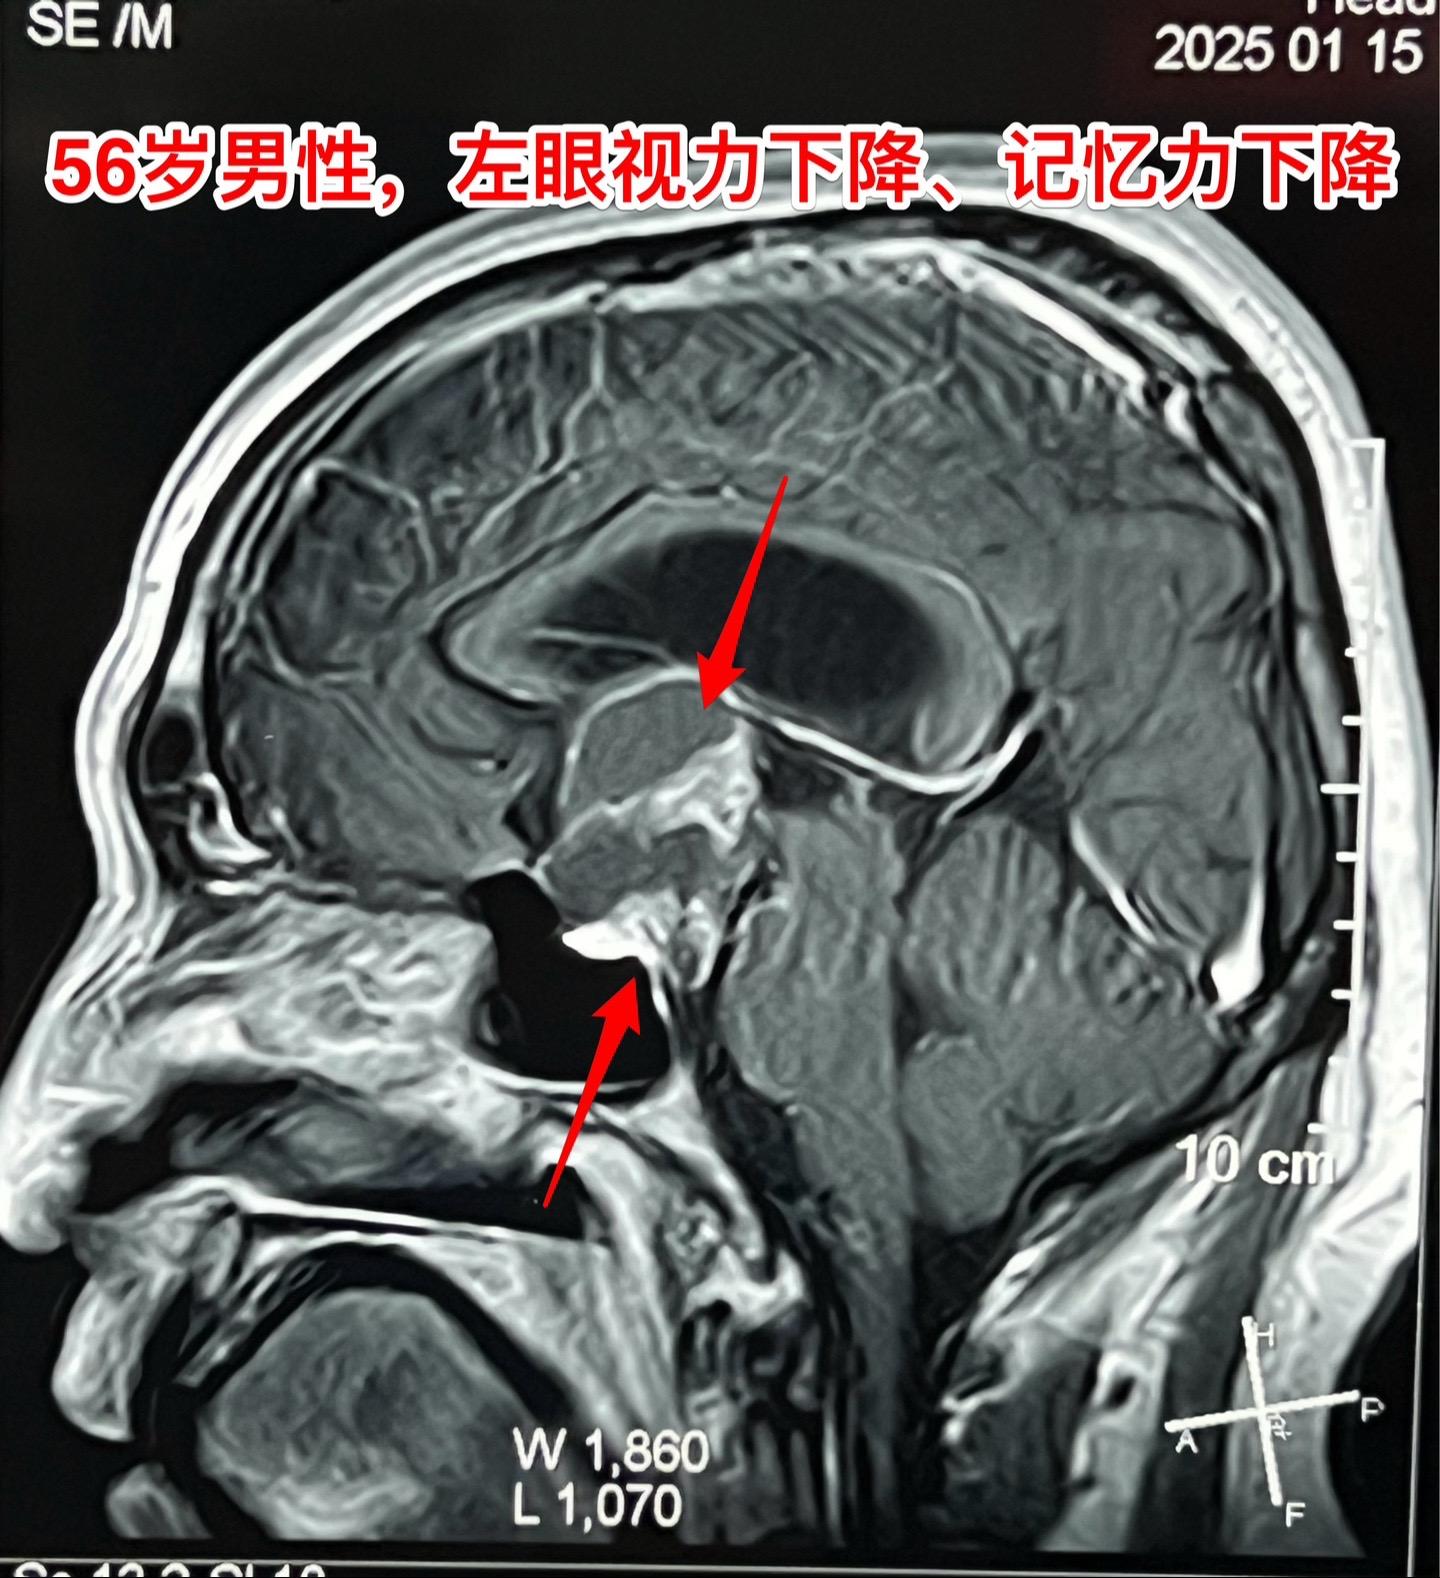

一天两个颅咽管瘤手术,凌晨两点才到家 科里年轻医生说还在关颅。 第一个病人广州人,56岁,左眼视力下降,检查出颅咽管瘤已经半年了,近期出现记忆力下降。病人之前一直在赶在过年前来作手术。今天的手术很顺利。 第二个病人是40岁大同市男性,思维糊涂、精神萎靡,坐轮椅到三博脑科医院就诊,颅咽管瘤伴有脑积水。今天的手术也是很顺利。